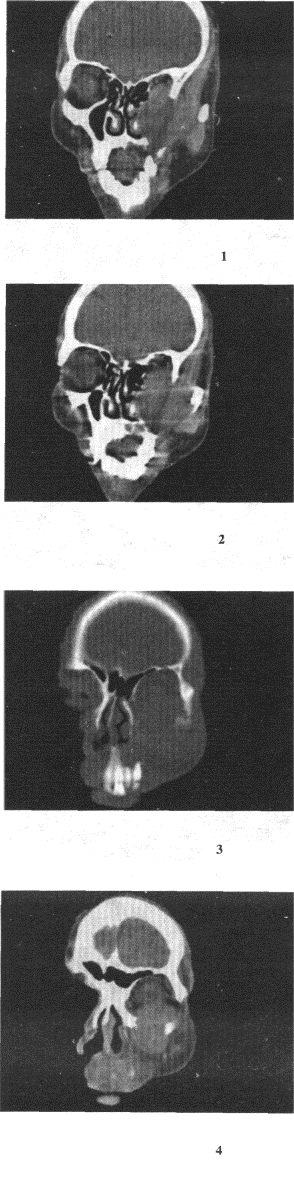

女,52岁,左眼球突出20余年,Ti、T2均正常,影像检查如图所示,最可能的诊断是() 错构瘤。 脂肪瘤。 畸胎瘤。 血管瘤。 炎性假瘤。

男,65岁,左眼球突出近1年,鼻涕带血,面颊部隆起,同时面颊部有麻木感,CT检查如图,最可能的诊断是()